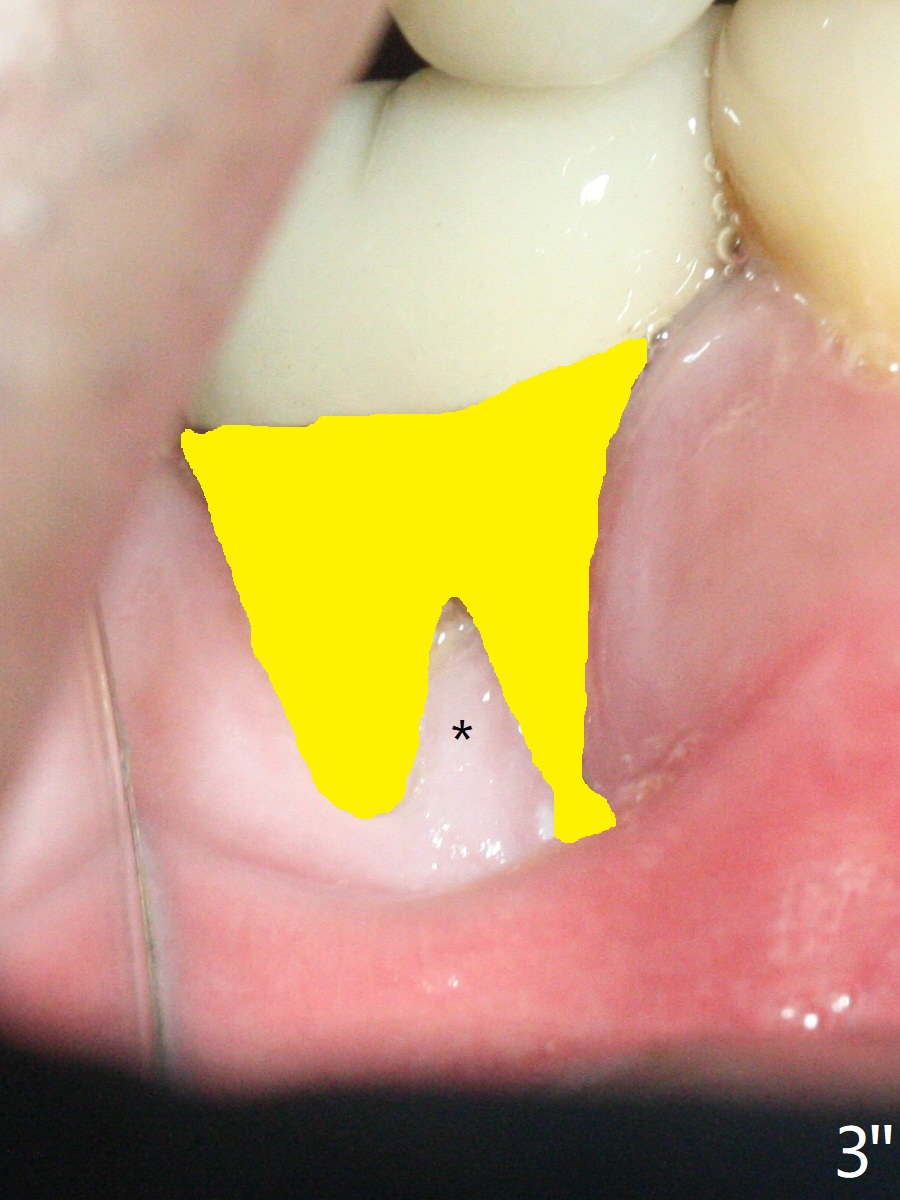

A 47-year-old man has poor dentition. The tooth #31 needs RCT, while #30 has severe PARL, especially mesial (Fig.1 M). The buccal roots are exposed (Fig.2). Between the exposed roots is the septal gingiva, which will be saved for buccal soft tissue repair (Fig.3 *). The septal gingiva will keep in place (not to be transferred) so that the recession will disappear by epithelial regrowth from the nearby gingiva (Fig.3' arrows) over the bone graft and PRF. The provisional should be fabricated to cover the soft tissue defect (Fig.3'' yellow area). In fact the mesial root fractures (Fig.4 ^), as related to the severe bony defect. There seems to be enough lingual bone to hold a 4x13 mm implant (Fig.5 green). Sticky bone (Fig.6 red circles) and PRF (blue) are to be used to repair the hard and soft tissue defects following an immediate provisional (Fig.5,6 yellow outline). Extra layer of acrylic (Fig.6 orange) will be used to cover the PRF buccally. The base of the buccal plate is thick (Fig.6 *); mesial portion appears to be denser (Fig.7 black *) than the distal one (white *). Decortication will be done if hemorrhage is insufficient. Fig.8 is a coronal section of the socket (B: buccal). Extraction (Fig.9 black area) will most likely result in a knife edge ridge. Extraction with bone graft may not fare better, as it is easy to lose the graft considering missing buccal hard and soft tissues.